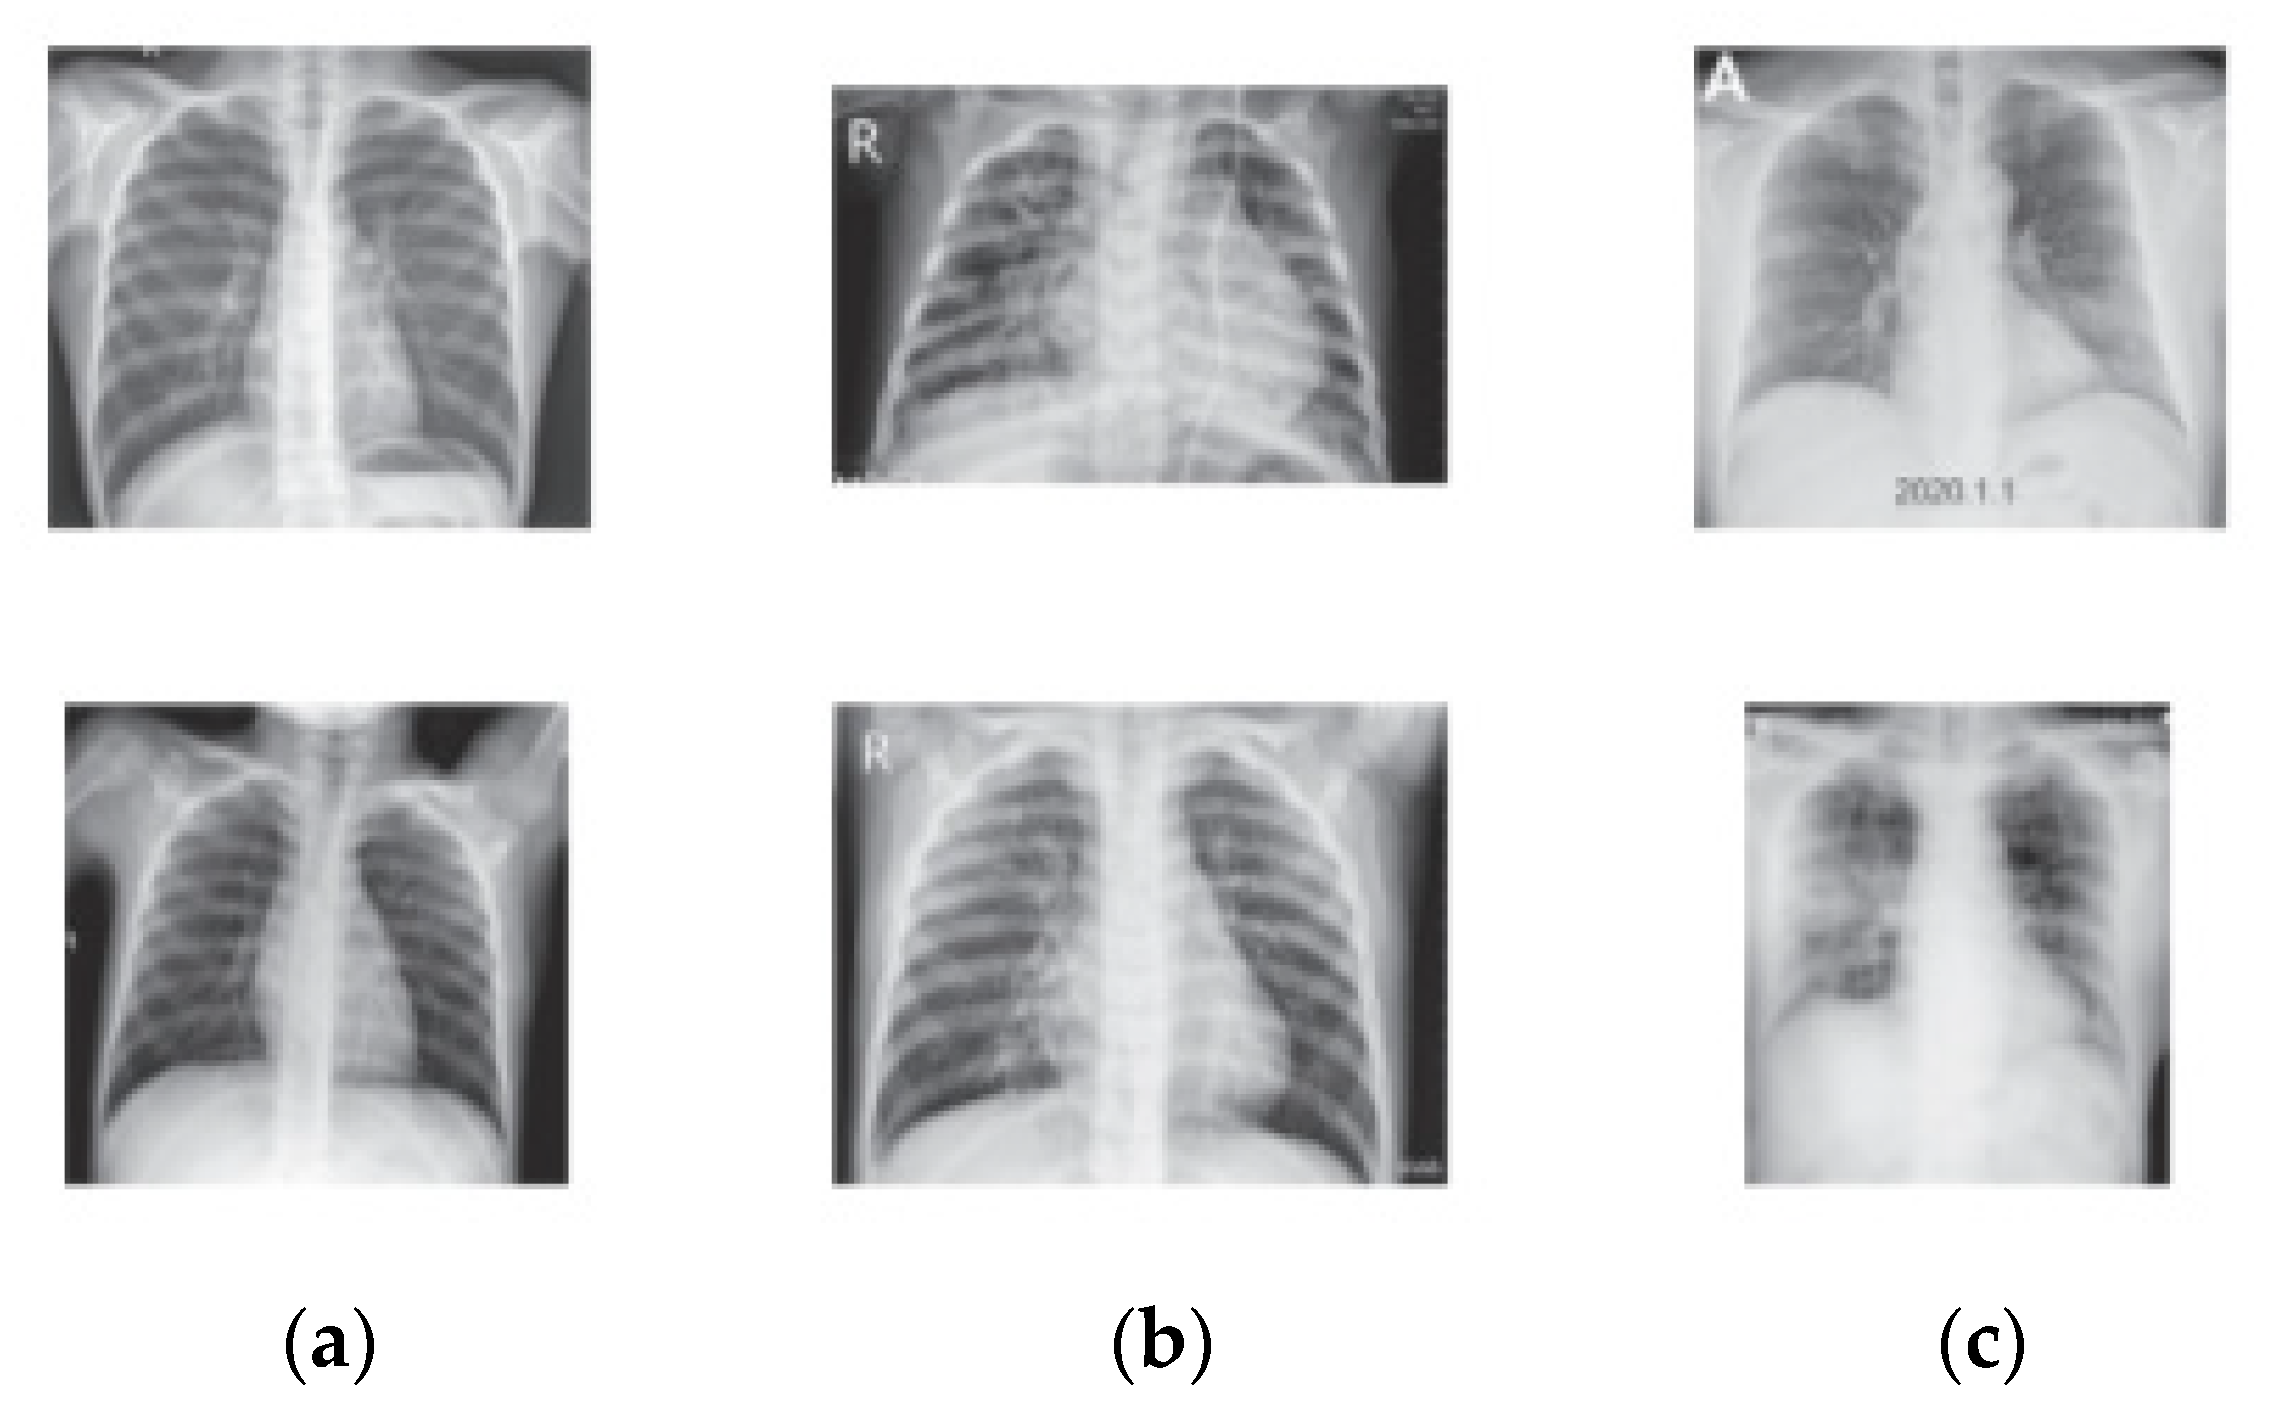

On the other hand, COVID-19 public dataset in [54] is also used to validate the proposed method. This dataset consists of 460 COVID-19, 1266 normal, and 3418 pneumonia training X-ray images and 116 COVID-19, 314 normal, and 855 pneumonias for testing. The main critical issue in this dataset is that it contains pneumonia that is caused by bacterial infection and not COVID-19. Figure 9 illustrates images that are randomly selected from the class samples.

Figure 9.

COVID-19 X-ray Samples: (a) Normal, (b) Pneumonia, (c) COVID-19.